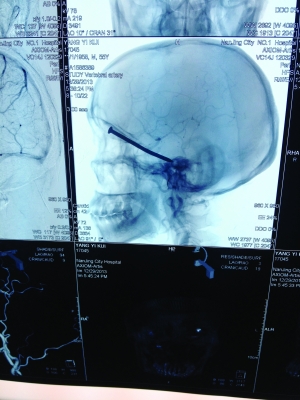

CT投影结果,把大家吓了一跳:杨先生脑子里居然有一根长钉,从眼眶一直“伸”到了接近后脑勺的位置!铁钉细长略带弯曲,长达8厘米。根据推测,铁钉应该是从上眼眶的缝隙中飞入,一直插进脑颅中,末端还有一个小小凸出的钉帽。

据南京市第一医院神经外科主任医师罗良生介绍,眼眶处虽然有骨头,但比较薄,如果钉子的飞行速度够快,就能轻易地穿透骨头进入头颅。“钉子进去后,可以看到它附近有很多重要神经和血管,比如视神经、颈内动脉,等等,一旦戳到任意一根,都会引起失明甚至大出血。而这根铁钉却避开了所有这些重要神经和血管,颅内也没有出血,这样的情况非常罕见,患者实在是太幸运了。”